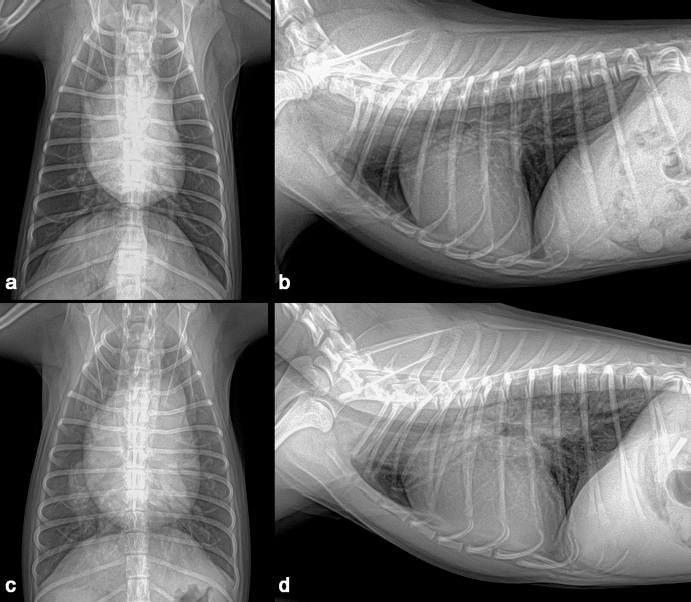

A 1-year-old neutered male Maltese dog weighing 1.4 kg was referred to the Veterinary Teaching Hospital showing microhepatica (Fig. 1a) and hyperammonemia. The dog did not show clinical signs related to portosystemic shunt previously. Although its postprandial ammonia level was in the reference range [18 μmol/l, reference interval (RI): 0–98 μmol/l], hypoalbuminemia (2.1 g/dl, RI: 2.6–3.3 g/dl) and increased levels of serum bile acid (177 μmol/l, RI: 0–25 μmol/l), alanine transaminase (ALT) (254 IU/l, RI: 21–102 IU/l), and alkaline phosphatase (ALP) (1347 IU/l, RI: 29–97 IU/l) were identified. No abnormalities, including cardiac murmur, were observed during physical examination. For a more thorough examination, computed tomography was used, and a CPSS (porto-caval shunt) was diagnosed (Fig. 2a and b). After preoperative medical stabilization, surgery was performed for shunt attenuation. Anesthesia was induced with propofol (8 mg/kg, IV) and maintained by isoflurane. Perioperative pain was managed by tramadol (5 mg/kg, IV). From the xiphoid process to the pubis, a standard ventral midline approach was taken. After dissecting the shunt from surrounding tissues, portal pressure was measured from the jejunal vein. Baseline portal pressure was measured to be approximately 7–8 mmHg (RI: 6–10 mmHg). It increased to 13–14 mmHg after temporary complete occlusion of the shunt. The shunt was attenuated using a cellophane band. The abdominal cavity was closed in a routine manner. Its recovery from anesthesia was uneventful. Postprandial serum bile acid (12 μmol/l), albumin (2.6 g/dl), and ALT (29 IU/l) levels returned to their normal ranges at 1 month after the operation. Its serum ALP level also decreased to 430 IU/l, although it was above the RI. An increase in liver size was observed by abdominal radiographs 1 month after surgery (Fig. 1b). Because the majority of the CPSS anomalies were cured throughout the follow-up period, the dog was able to return to normal life without the need for supporting medicine. One year after surgery, the dog was presented to the Veterinary Teaching Hospital for exercise intolerance. Blood gas analysis revealed hypoxemia (73.6%, RI: 95%–99%). A cardiac murmur was auscultated. When compared with thoracic radiographs evaluated at the time of the operation (Fig. 3a and b), the vertebral heart scale increased from 10 to 11.7, indicating generalized cardiomegaly (Fig. 3c and d). Following echocardiography revealed ASD and pulmonary hypertension (Fig. 4a and b). A bubble study confirmed right-to-left shunt. Surgical or interventional therapy was not contemplated due to the dog's tiny size (1.7 kg) and reversed interatrial shunt. Thus, medical treatment was performed to reduce pulmonary hypertension (sildenafil, 1.5 mg/kg, PO, q12 hours). Hypoxemia was improved (94%) after a month of treatment. The dog's activity intolerance had been overcome, according to the owner. As a response to the medical treatment was generally good, therapy was still maintained without changing medication for the next 16 months after diagnosis of the ASD.

Fig. 1. Preoperative abdominal radiograph revealed microhepatica (a). An increased liver size was seen in abdominal radiograph one month after the operation (b).

Fig. 3. Thoracic radiographs. When compared with preoperative images (a, b), generalized cardiomegaly was observed at one year after the operation (c, d).